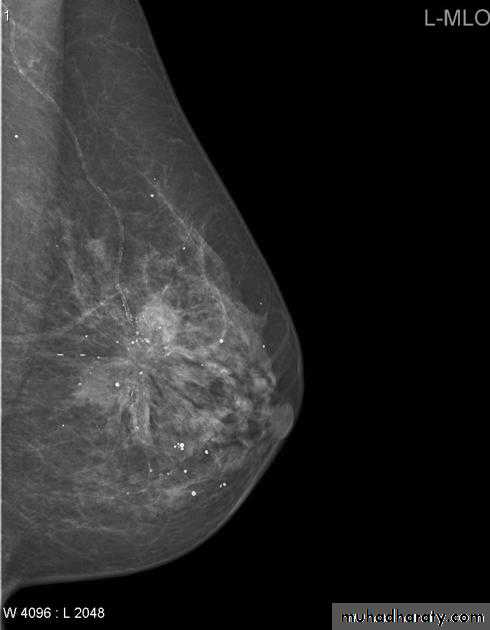

A…..Invasive ductal carcinoma is a subset of ductal carcinoma. It is an infiltrating, malignant and abnormal proliferation of neoplastic cells in the breast tissues. It is the most frequently seen breast malignancy .Radiographic features

Mammogramspiculated hyperdense lesion

oval/lobulated lesion

microcalicifications